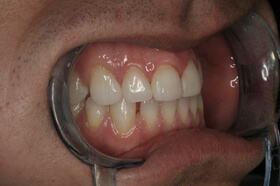

Agresszív fogágybetegség miatt kialakult frontfog elmozdulás – oldalnézet